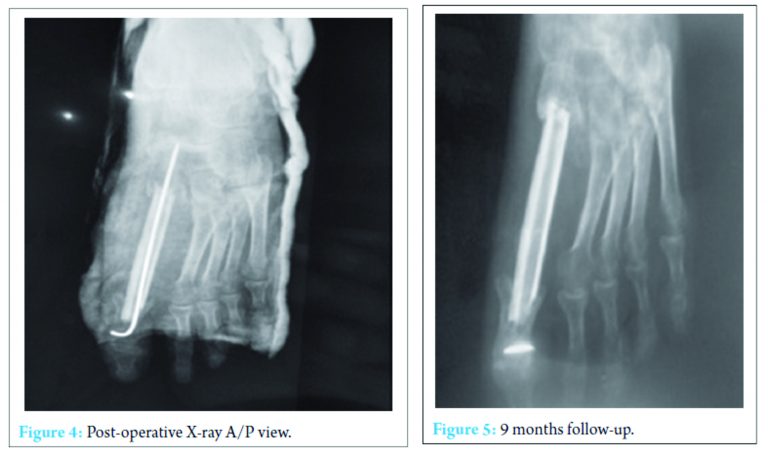

A reconstructive surgery with fusion of the Cuneiform metatarsal and metatarsophalangeal joint was planned. The tumor was carefully removed with a cuff of normal tissue and the proximal and distal joints were inspected. There was no articular cartilage of the Cuneiform metatarsa joint. A fibular graft was taken and was inserted into the troughs created in medial cuineform and proximal phalanx and fixed with K-wire, both proximally and distally (Fig. 3 and 4) [10].

The patient was given a below knee cast for three months postoperatively. Full weight bearing was started after 3 months. After 9 months of follow-up, the graft was well taken up and there were no signs of recurrence both clinically and radiologically (Fig. 5).